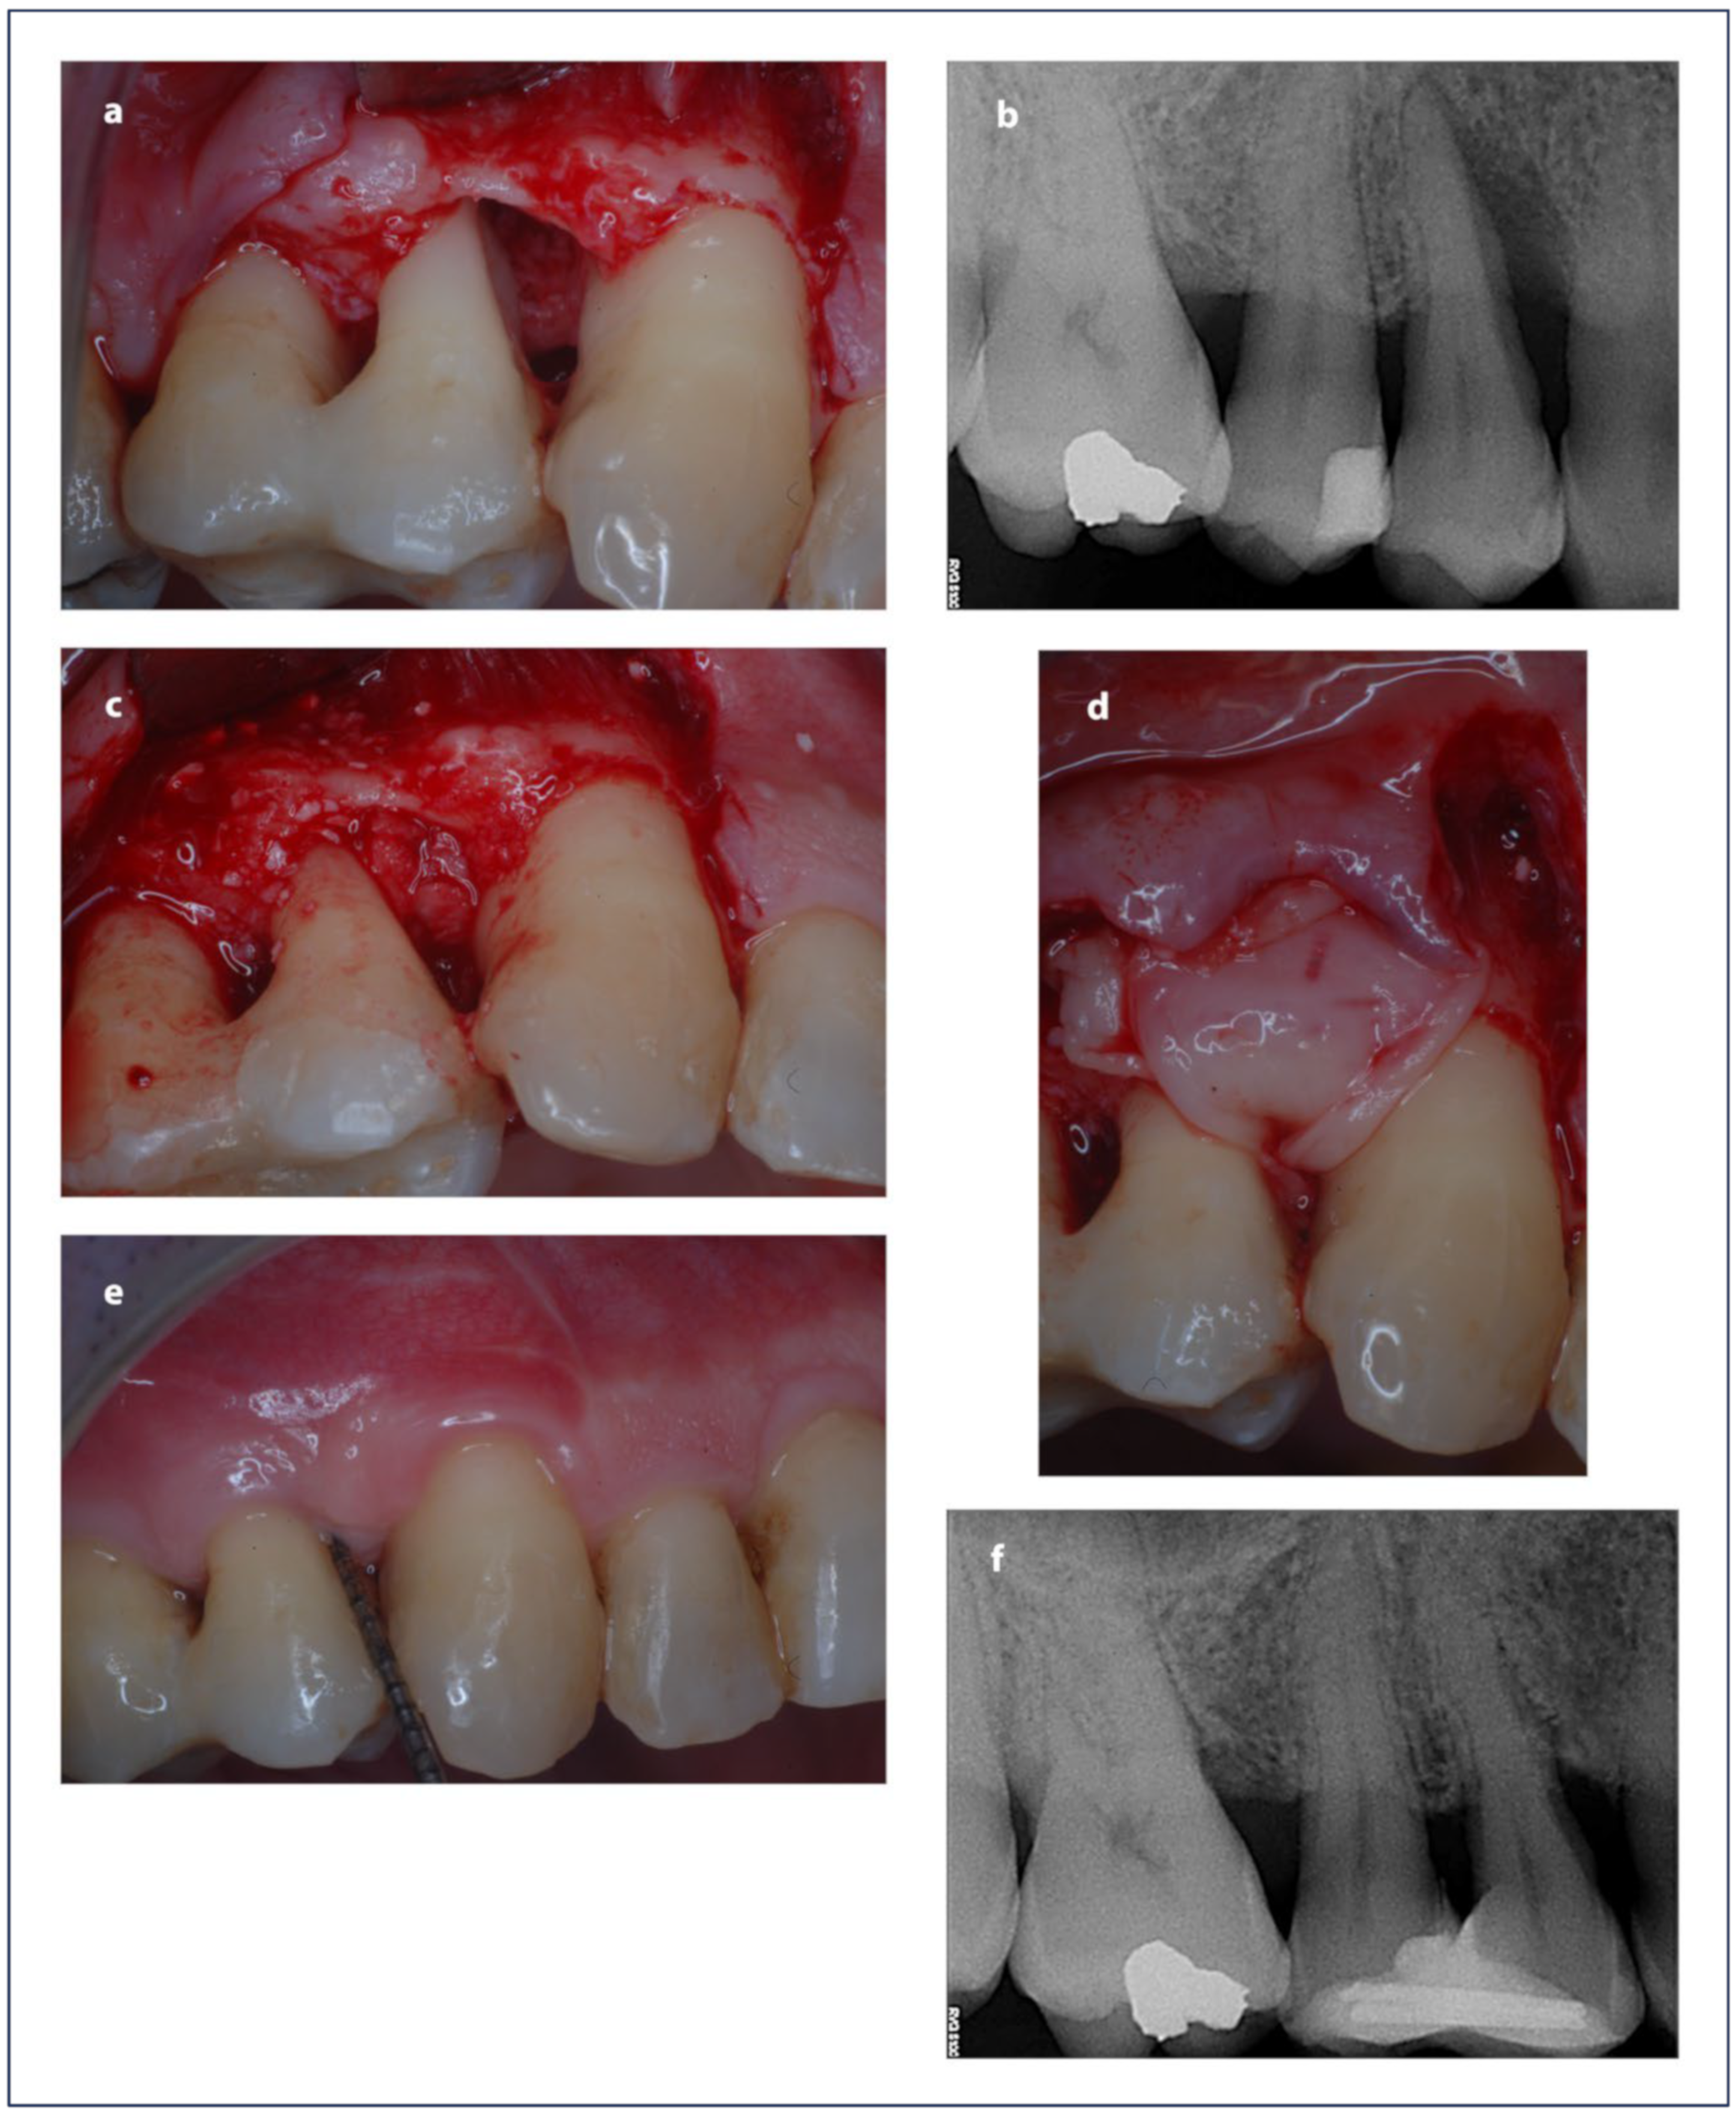

2.9. Surgical Procedure

3. Results

3.2. Clinical and Radiographic Outcomes